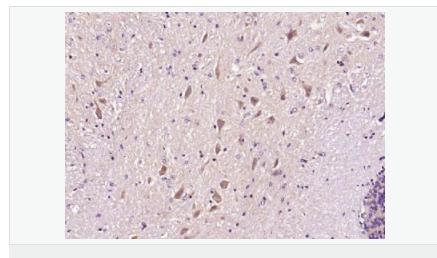

產(chǎn)品應用WB=1:500-2000 ELISA=1:5000-10000 IHC-P=1:100-500 IHC-F=1:100-500 Flow-Cyt=1ug/Test IF=1:100-500 (石蠟切片需做抗原修復)

Synuclein 包括α-Synuclein,β-Synuclein 和γ-Synuclein 是神經(jīng)細胞中富含的前突觸蛋白。α-Synuclein,Alzheimer’(AD)病淀粉樣蛋白沉積的成份之一,集中分布在神經(jīng)細胞的包體和突觸。在帕金森病人中發(fā)現(xiàn)有α-Synuclein的變異型,而γ-Synuclein與軸突病理學有關。此抗體將為Lewy小體癡呆癥、Parkinson癥、AD和其它一些神經(jīng)性疾病提供有用的病理診斷。